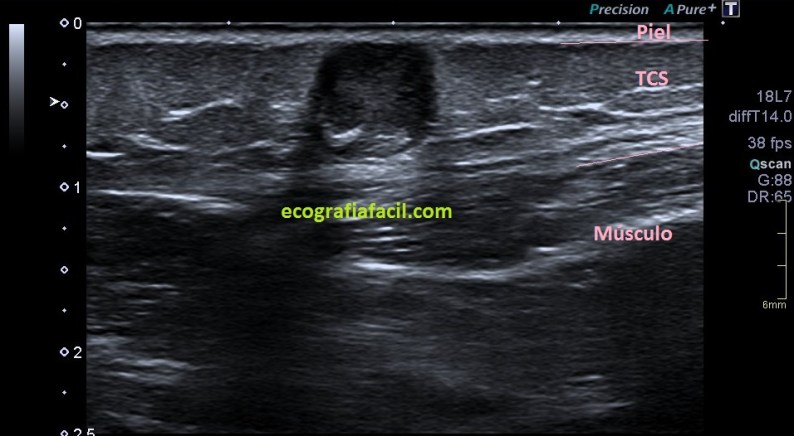

Lo primero que quiero que tengas en cuenta es la localización del bulto, ves que es supersuperficial. Para estudiar este tipo de lesiones lo que debes hacer es tener una buena capa de gel sobre el tumor. Esto se hace con efecto de apoyar la sonda sobre el gel y no sobre la piel para no deformar la lesión, así que es muy importante la técnica y pericia de la operadora que esté ejecutando el estudio.

Lo segundo es localizarlo perfectamente en su ubicación, y ver a qué planos pertenece, si está tocando o no la estructuras que están a su alrededor. En el caso de esta lesión vemos que está en justo debajo de la piel, en el escaso espesor de tejido celular subcutáneo que existe en la región frontal, que es donde la mujer tenía este tumor.

Tercero y último. Ahora lo medimos y lo estudiamos ecográficamente, acotándolo. La semiología es importante, en este caso, el tumor tiene un aspecto hipoecogénico, pero en el centro es hiperecogénico, pero además, dentro de esta hiperecogenicidad existe un grado más de hiperecogenicidad perteneciente a una calcificación grosera. Sus bordes son definidos y con la salvedad de las zonas de calcio, el tumor transmite bien. Su aspecto es heterogéneo, no presenta vascularización, la que ves en la imagen es artefacto de aliasing provocado por el calcio de la lesión.